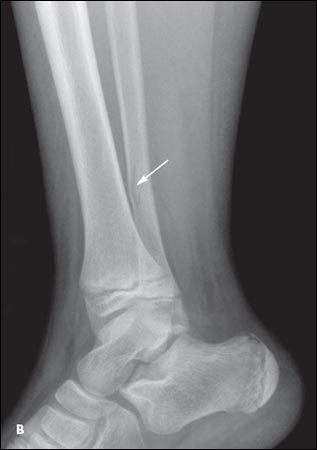

While playing on the school playground, a 10-year-old boy decided to try a zip line (Figure 1). He grabbed the pulley and slid down the cable. When the pulley came to a stop, he fell off and sustained a right ankle injury. In the emergency department (ED), the diagnosis was a right distal fibula shaft fracture and distal/medial Salter-Harris type II tibia fracture (Figure 2). The fractures were nondisplaced, and the child's right lower extremity was placed in a long leg cast, which was replaced 3 weeks later with a short walking cast; he was transitioned to a walker boot 2 weeks after that. The fractures healed without complications. Because of possible injury to the growth plate, follow-up in 6 to 9 months was needed to ensure there was no physeal arrest.

Figure 2 – Anteroposterior (

A

) and lateral (

B

) radiographs taken in the emergency department show a right distal fibula shaft fracture and distal/medial Salter-Harris type II tibia fracture.